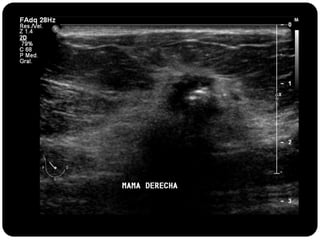

Paciente femenina de 66 años con historia clínica de 1er gesta antes de los 30 años y antecedentes de lactancia positiva, presenta una lesión palpable en la mama derecha. Los estudios radiológicos indican un diagnóstico de bi-rads 5, con biopsias revelando adenocarcinoma lobulillar infiltrante en la glándula mamaria derecha y adenocarcinoma ductal in situ en la izquierda. El caso fue evaluado por las doctoras Jacqueline Preciado Vargas y Beatriz E. González Ulloa.